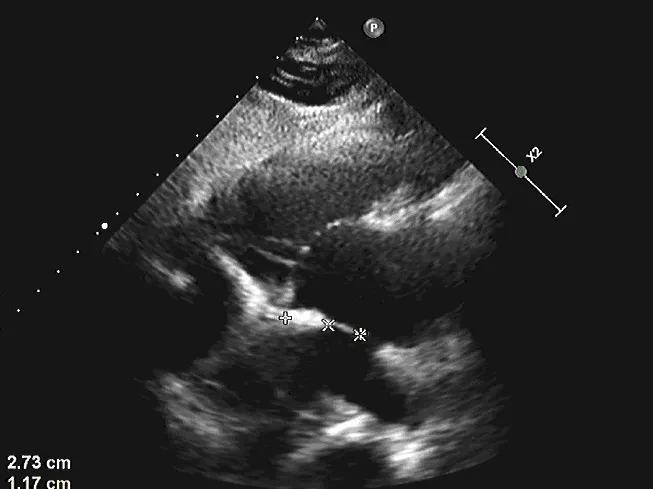

术中复测:术中食道超声下复测缺损大小,缺损大小为14.5mm,合并软缘11.7mm,其他边缘充足。

术中复测

术中测量软缘长度

术中复测缺损大小

剑下双房心切面测量上腔静脉侧边缘